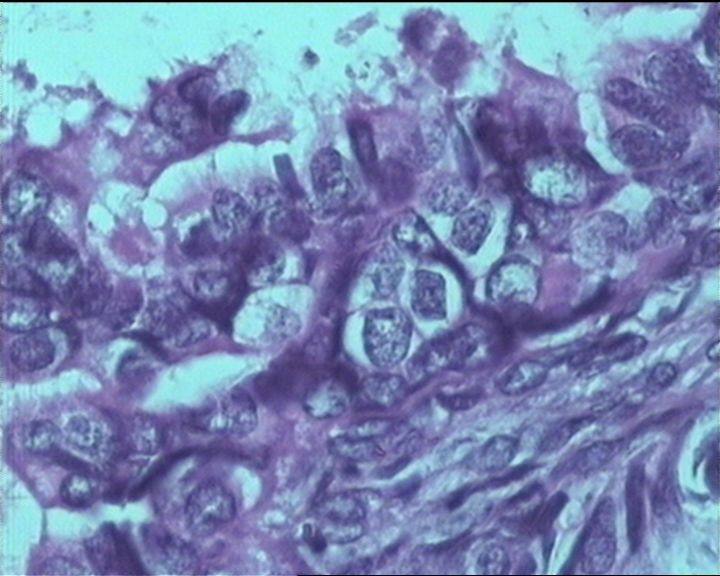

54岁女性,临床“宫颈息肉”送检;巨检:组织一块1。5*1CM,灰红。